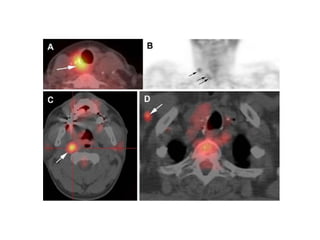

 6% al23% del total de pacientes con CA diferenciado, desarrollan metástasis a distancia.  1% al 4% son evidentes al momento del diagnóstico.  Pacientes con mets a distancia tienen una sobrevida a 5 años del 50%.  El sitio más frecuente es el pulmón, seguidos de hueso, menos frecuentes, cerebro, hígado y piel.  Factores que predicen un peor pronóstico son:  Síntomas, edad >45 años, y poco captación de yodo.

 La cirugíaes un buen tratamiento paliativo en metástasis localizadas, sintomáticas y resecables.  Otra terapia ampliamente utilizada es la radioterapia, la cual en un porcentaje aceptable mantiene controladas las metástasis especialmente en hueso.  El pilar del tratamiento de las mets es la terapia con Yodo radiactivo.

 En lasmets pulmonares algunos factores que mejor el pronostico son: paciente joven, tumor pequeño y sensible al yodo.  El tratamiento con yodo es mas efectivo en las mets a pulmón que en hueso.  Las mets a hueso son más comunes a en el CFT (vértebras, pelvis y costillas son los sitios más afectados).  Considerar cirugía o radioterapia si existen síntomas.  Las mets a cerebro son raras no hay consenso si es mejor el tratamiento de éstas.